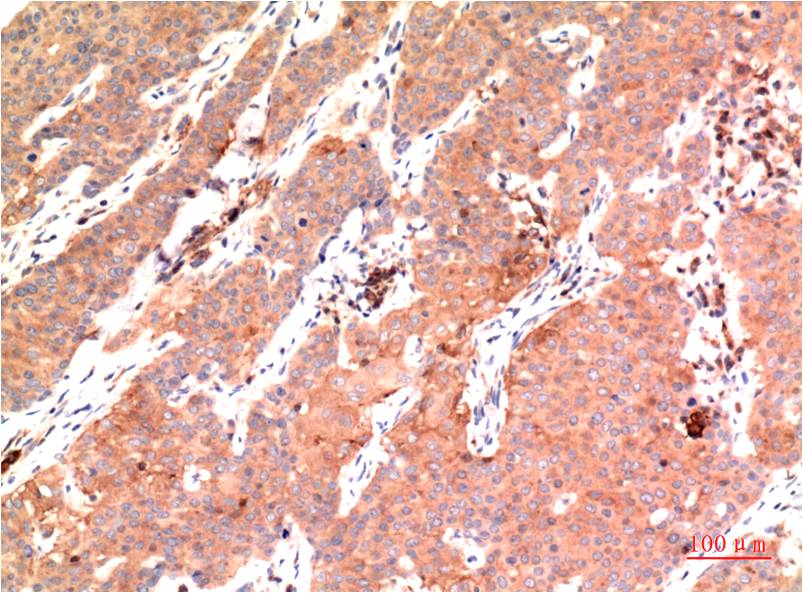

Immunohistochemistry analysis of paraffin-embedded Human Colon Carcinoma Tissue using epsilon Tubulin antibody.High-pressure and temperature Sodium Citrate pH 6.0 was used for antigen retrieval. |